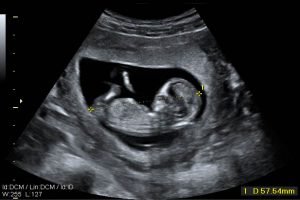

Diplomados en Ultrasonografía